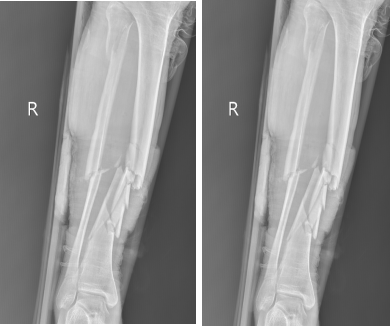

67岁的戎先生在家中不慎摔伤,致右胫腓骨开放性粉碎性骨折。

[术前检查]

外固定支架创伤小更有利于术后恢复,对于开放性骨折或感染无法第一时间进行内固定的患者,外固定支架无异于最优选择,外固定支架已广泛应用于治疗骨折、矫治骨与关节畸形和肢体组织延长。